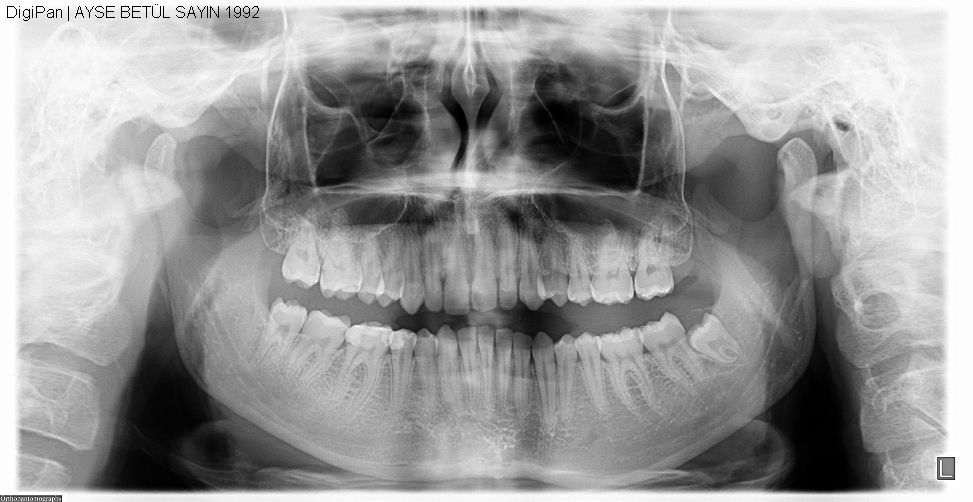

YİRMİ YAŞ DİŞLERİ (Akıl Dişleri):

Ağzımızda en son süren dişler yirmi yaş dişleridir. Bazı kişilerde de doğuştan hiç yirmi yaş dişi germi oluşmamıştır. Dolayısıyla bu kişilerde yirmi yaş dişleri hiçbir zaman sürmez. Ancak bazen bu dişler oluştukları halde sürme problemleri oluştururlar. Çenede yer olmaması veya çeşitli nedenlerle yirmi yaş dişlerini çekmek gerekebilir.

Genelde 17 ile 25 yaşları arasında sürmeye başlar. Eğer doğru pozisyonda sürmüş, diğer dişlere baskı yapmıyor, çevre dokulara zarar vermiyorsa ve ağız hijyeninin sağlanmasında engel teşkil etmiyorsa  bu dişin yerinde kalmasında bir sakınca yoktur.